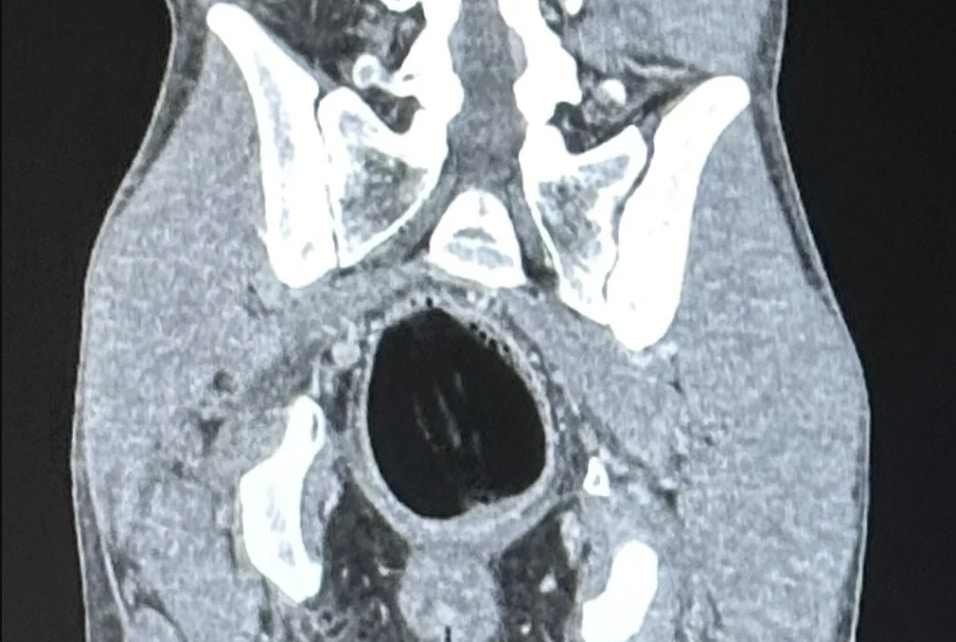

Σύμφωνα με πληροφορίες του tempo24.news, ο άνδρας πήγε μόνος του στο Νοσοκομείο ενώ σύμφωνα με άλλες  πληροφορίες του protinews.com.gr ο 30χρονος χρειάστηκε να μπει στο χειρουργείο καθώς είχε ένα μήλο στον πρωκτό του.

Η ύπαρξη μήλου στον πρωκτό του νεαρού επιβεβαιώθηκε και από τις εξετάσεις… και αμέσως κλήθηκε χειρουργός για να πραγματοποιηθεί επέμβαση.